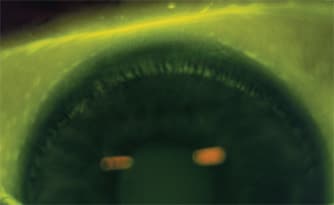

Figure 2. Peripheral staining, usually a continuous paralimbal/limbal annulus. We considered staining peripheral when the average extent of staining in the peripheral corneal zones was more than 0.5 of a unit higher than the central zone.

Solution-induced Corneal Staining (SICS): diffuse punctate staining (extent grade 1 and above) in at least four of the five regions (central, superior, inferior, nasal and temporal) of the cornea. Conjunctival staining extending from the limbus to the lens edge may also be present. There are normally two presentations of this type of staining: diffuse and peripheral (Figures 1 and 2). Figures 3 and 4 show differential diagnoses of peripheral SICS from dehydration staining and limbal transition pooling.